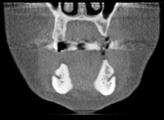

Målinger af pladsforholdene posteriort i en atrofisk mandibel

af processus alveolaris til canalis mandibulae på et CBCT-snit i det koronale plan (ca. 14 mm). C. Længdemål fra tværlinje (grøn), hvor bredden af processus alveolaris er 8 mm, til canalis mandibulae på samme CBCT-snit (ca. 5 mm).

Fig. 3. A. Vertical measurement from the top of the alveolar ridge to the mandibular canal in a CBCT section in the sagittal plane (approximately 13 mm). B. Vertical measurement from the top of the alveolar ridge to the mandibular canal in a CBCT section in the coronal plane (approximately 14 mm). C. Vertical measurement from horizontal line (green), where the width of the alveolar ridge is 8 mm, to the mandibular canal in the same CBCT section (approx. 5 mm).

Fig. 2. Fossa submandibularis (markeret med pile) ses oralt i den posteriore del af mandiblen på en 3-d-model i et softwareprogram til analyse af CBCTscanninger. Fig. 2. The submandibular fossa (marked with arrows) is located lingually in the posterior part of the mandible on a 3D model in a software program for analysis of CBCT scans. Fig. 3. A. Længdemål fra toppen af processus alveolaris til canalis mandibulae på et CBCT-snit i det sagittale plan (ca. 13 mm). B. Længdemål fra toppen

Da et implantat ideelt set skal være omgivet af 1-2 mm knogle langs hele implantatoverfladen, vil der i tilfælde af en smal knoglekam være risiko for, at implantatet bliver placeret dybt, hvor implantatets skulder således forsænkes i forhold til den mest marginale begrænsning af processus alveolaris. Dette kan bl.a. medføre en uhensigtsmæssig krone-implantat-ratio. Klinisk og radiologisk vurdering af knoglens bredde er derfor også nødvendig for at kunne bestemme den mest optimale implantatlængde, inklusive om der er behov for horisontal knogleopbygning enten før eller i forbindelse med implantatindsættelsen (Fig. 3). Dette er naturligvis ikke muligt med todimensionale (2-d) røntgenoptagelser, og en klinisk vurdering af breddeforholdene med palpation og evt. ”ridge mapping” (9) eller ved hjælp af tredimensionale (3-d) røntgenoptagelser vil derfor ofte være nødvendig. Det skal her nævnes, at en 3-d-optagelse også kan afklare, hvordan canalis mandibulae er orienteret i det facioorale plan, hvilket ligeledes kan influere på behandlingsplanlægningen.

tværsnitsbilleder. Et tip til, hvorledes man kan lette identifikationen, er i det koronale plan først at identificere foramen mandibulae posteriort. Herefter ”bladrer” man gennem de koronale tværsnit posteriort fra i anterior retning mod implantatstedet og holder øje med canalis mandibulae hele vejen. Alternativt kan man lokalisere foramen mentale og bevæge sig i posterior retning (Fig. 4). Ved hjælp af scanningssoftwaren kan canalis mandibulae oftest indtegnes, således at kanalen kan følges i alle snitplanerne (Fig. 4).

På CBCT-optagelser ses der i praksis ingen projektionsforstørrelse, og målingerne foretaget ved hjælp af scanningssoftwarens måleværktøj anses for målfaste. I mange af softwareprogrammerne, som findes på markedet, kan man gøre brug af såkaldte implantat-attrapper i forskellige størrelser og design og derved foretage en virtuel implantatindsættelse før operationen (Fig. 6).

Implantatattrapper indsat i koronale CBCT-snit

Omhyggelig planlægning før implantatbehandling er afgørende for at kunne træffe det rigtige valg i forhold til behandlingsmetode samt sikre et forudsigeligt behandlingsresultat med en god langtidsprognose og mindst mulig risiko for komplikationer. Dimensionerne, pladsforholdene i mandiblen og afstanden fra toppen af processus alveolaris til den øvre begrænsning af canalis mandibulae er de væsentlige parametre, som har betydning for valg af behandling. I dette temanummer vil tre behandlingsteknikker, som kan anvendes i den atrofiske posteriore mandibel, blive nærmere gennemgået involverende transposition eller lateralisering af NAI (ved en højde af processus alveolaris på ca. 0-4 mm), sandwich-osteotomi (højde på ca. 4-8 mm) og indsættelse af korte implantater (højde på > ca. 8 mm) (Fig. 7). De undersøgelsesmetoder, man vælger i forbindelse med behandlingsplanlægningen, skal gerne være til gavn for patienten og med færrest mulige ulemper. Man skal derfor arbejde

Fig. 6. A. Virtuel planlægning med en implantatattrap (5 x 7 mm) i præmolarregionen, hvor der tages hensyn til den smalle processus alveolaris og beliggenheden af canalis mandibulae (markeret med gule pile). Horisontal knogleopbygning kan være relevant i dette tilfælde for at undgå den dybe placering af implantatskulderen. B. Implantatattrap (5 x 5 mm) indsat i molarregionen med en sikkerhedsmargen til canalis mandibulae (gule pile). Fig. 6. A. Virtual planning with an implant dummy (5 x 7 mm) in the premolar region, where the narrow alveolar ridge and the location of the mandibular canal (marked with yellow arrows) are taken into account. Horizontal bone augmentation may be relevant in this case to avoid the deep placement of the implant shoulder.

B. An implant dummy (5 x 5 mm) placed in the molar region with a safety margin to the mandibular canal (yellow arrows).

I den atrofiske posteriore mandibel, som er karakteriseret ved en væsentlig reduktion af processus alveolaris’ dimensioner og formindsket plads til implantater, skønnes det, at CBCT ofte er indiceret ved behandlingsplanlægningen, da dette værktøj bedst kan visualisere de relevante anatomiske strukturer og give pålidelige mål, samtidig med at knoglens bredde kan bestemmes.